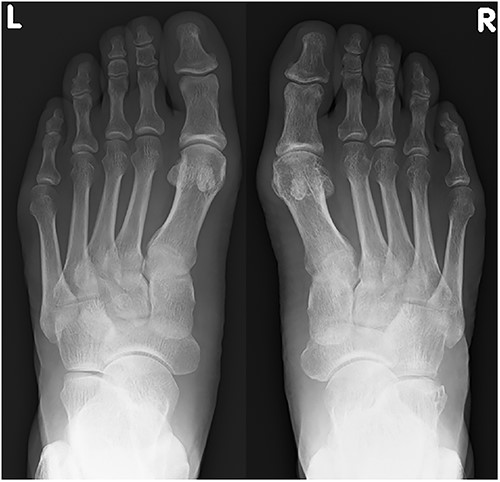

A 57-year-old carpenter fell from a height of 6 m and hit the right half of his body. He visited the emergency department of our hospital the same day. Physical examination revealed tenderness, swelling and deformity in the right foot (Fig. 1). Plain radiography, computed tomography (CT) and three-dimensional (3D) CT showed an uncommon injury; lateral dislocation of the naviculocuneiform joint, lateral dislocation of the calcaneocuboid joint, compression fracture of the calcaneus and avulsion fracture of the cuboid in the right foot (Figs 2 and 3). The next day, we attempted closed reduction, but the reduction was unstable. Percutaneous fixation with Kirschner wires (K-wires) was performed to stabilize the dislocated fragments. Two 1.5-mm K-wires were inserted from the navicular and cuboid bones to the medial cuneiform and calcaneus bones, respectively, and the dislocated joints were stabilized (Fig. 4). Postoperatively, the foot was immobilized with a below-knee splint. Mild ankle exercise was initiated in the early postoperative phase. The K-wires were removed at 8 weeks. Full weight-bearing was started at 14 weeks, and he was able to walk without pain. At 19 weeks, he returned to his job. At 1 year after the operation, the American Orthopaedic Foot and Ankle Society midfoot score was 75/100 points. He had mild and occasional pain, but he could walk about 2000 steps consecutively with no support or difficulty, and he had no marked limitation of daily activities. Fracture dislocation sites were stable on plain radiography (Fig. 5).

Plain radiograph at 1 year after the initial operation. There was no marked malalignment in the right foot.